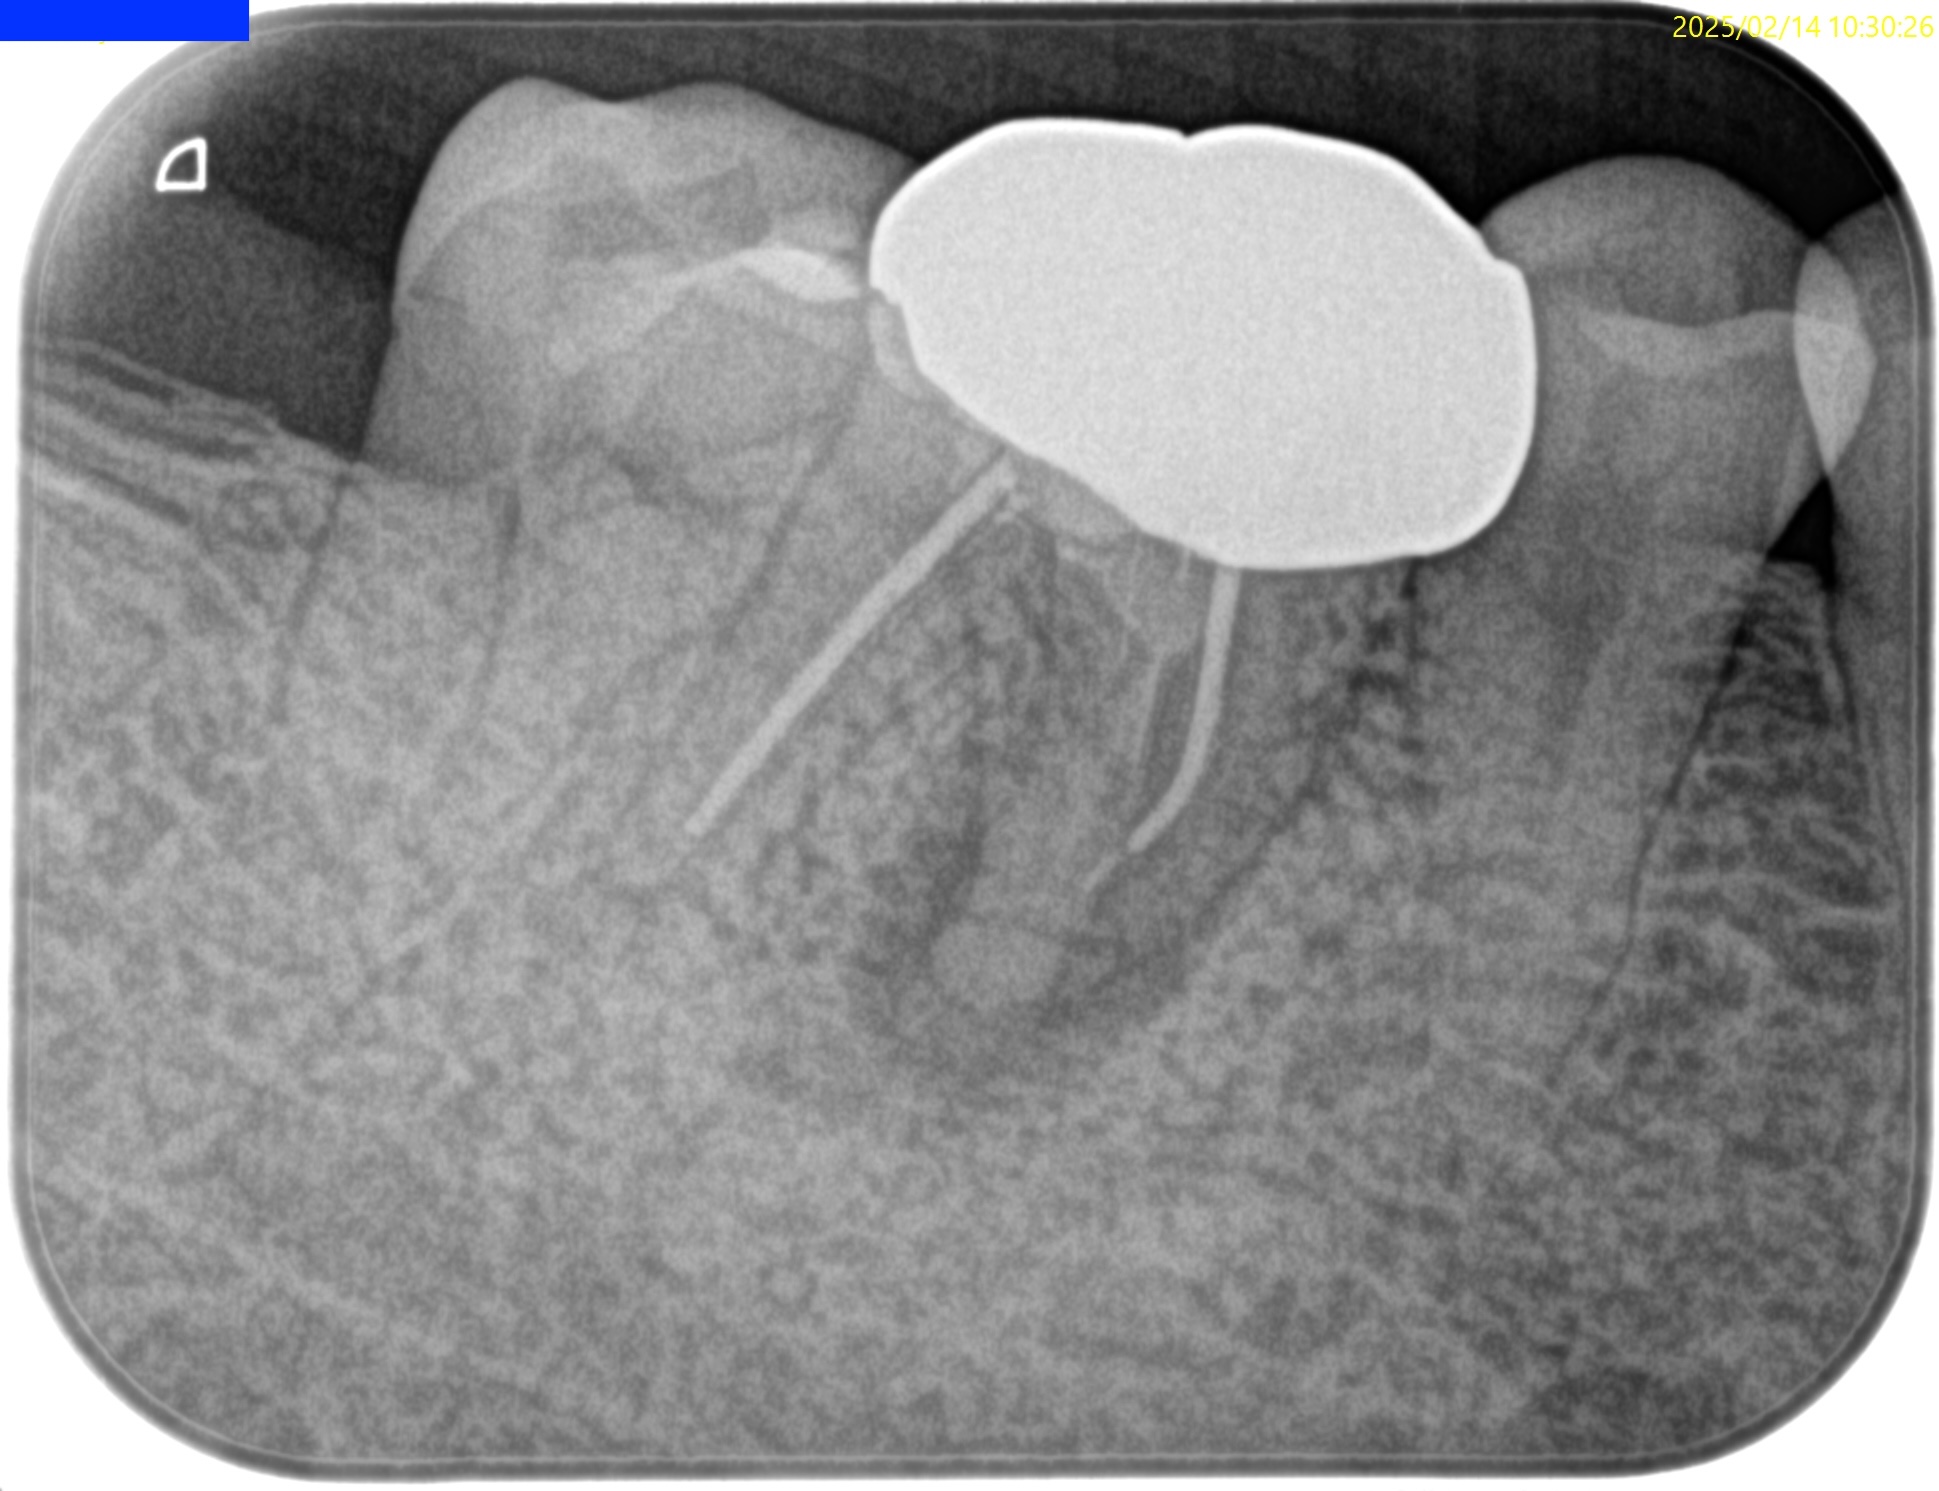

Pre-op Endo test(2025.2.14)

そこそこ湾曲度合いが強いRadix Entomolarisを有する#30だ。

が、D以外の根管はほぼ適切な根管治療がなされていない。

Radixにおいては未着手だ。

支台築造後にPA, CBCTを撮影した。

MB

ML

D

Radix

問題はないだろう。